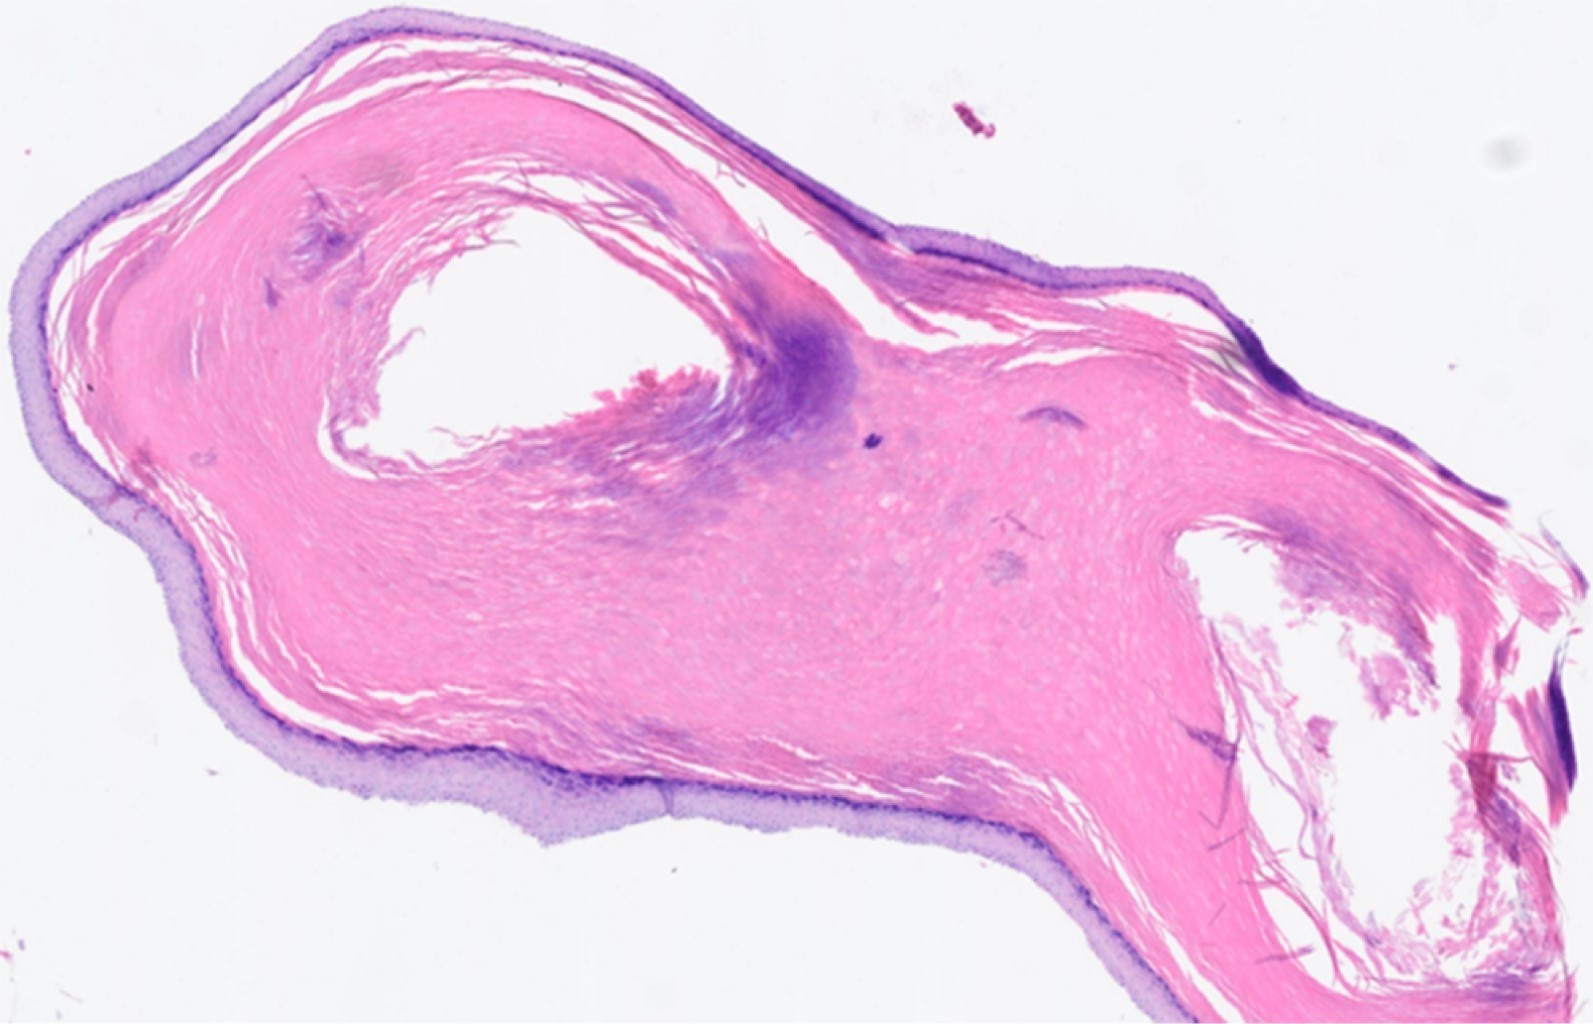

La evolución postoperatoria fue buena tanto clínica como analíticamente. Los cultivos fueron negativos. Fue la anatomía patológica la que sugirió la presencia de un quiste epidermoide sobreinfectado (Figura 2). Actualmente la paciente lleva seis meses de evolución, con correcto estado local y remodelación ósea (Figura 3).

Figura 3